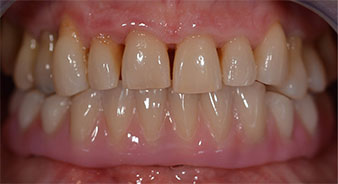

La patiente âgée de 64 ans présente une denture résiduelle des dents 38, 33 et 43 et une prothèse amovible mandibulaire stabilisée par crochets (Fig. 1 et 2).

Fig. 2